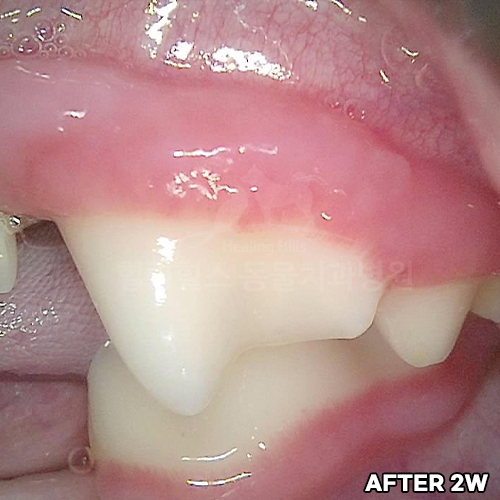

[강아지 치주염 치료 후 2주 경과]

[심한 치주염 치료 후 2주 경과]